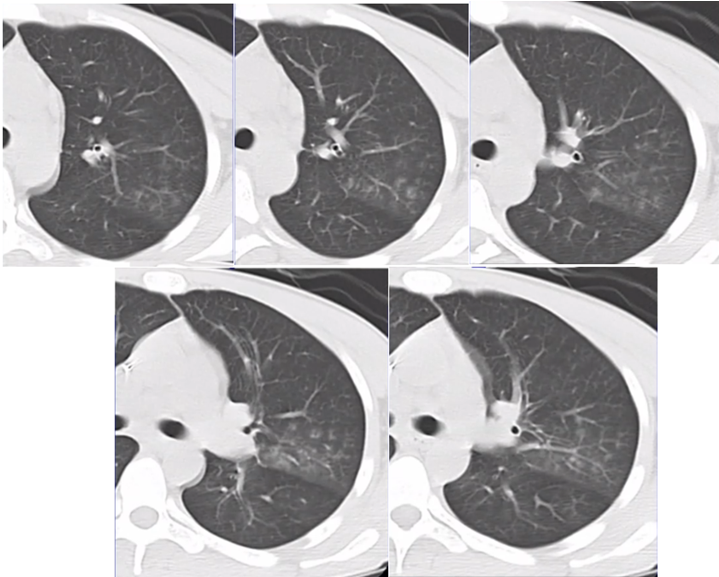

即使采取了广泛覆盖革兰氏阴性菌和阳性菌的多药联合的抗感染治疗策略,病变仍然不断进展,周围晕征不断扩大,实变成分增加,内见低密度影(图4)

图片

图4  患者胸部CT(2014-07-31)